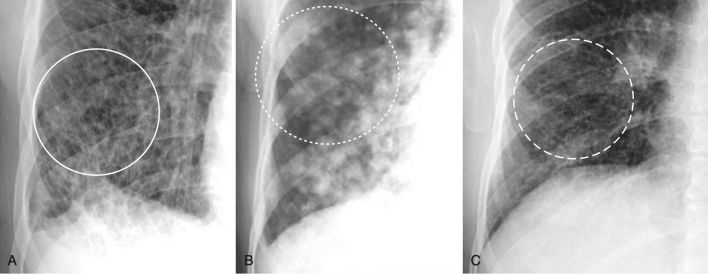

- Bệnh phổi mô kẽ tạo ra những cấu trúc có thể được coi là “phần tử” (“particles”) bệnh rời rạc xuất hiện trong mạng lưới kẽ phong phú của phổi (Hình 8 ).

- Các “phần tử” bệnh này có thể được đặc trưng hơn nữa là có ba dạng biểu hiện:

- Bệnh kẽ lưới (reticular) biểu hiện như một mạng lưới các đường kẽ (xem Hình 8, A).

- Bệnh kẽ hạt (nodular) biểu hiện dưới dạng các chấm (xem Hình 8, B).

- Bệnh kẽ lưới hạt có cả các đường và các chấm (xem Hình 8, C).

- Những “phần tử” bệnh lý kẽ này có xu hướng không đồng nhất, tách biệt với nhau bởi những vùng phổi được thông khí bình thường.

- Các bờ của bệnh phổi kẽ rõ nét hơn so với các ranh giới của bệnh khoang chứa khí (thường không phân biệt rõ).